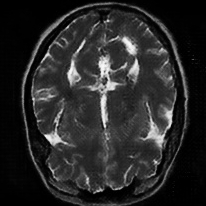

4.4 Qualitative Evaluation

In Figure 5 we analyze the prediction quality of our and compared approaches in a qualitative way. Considering modality propagation in MRI, we see that usage of uncertainty-aware patch invariance (UAPI) gives a better detailed weighting of the cerebrospinal fluid in the middle of the brain. In general, employing patch invariance yields better preservation of fine structures. This observation also applies to accelerated MRI enhancement. In particular, CUT and UAPI provide comparatively sharper knee images with more high-frequency details than the other methods.